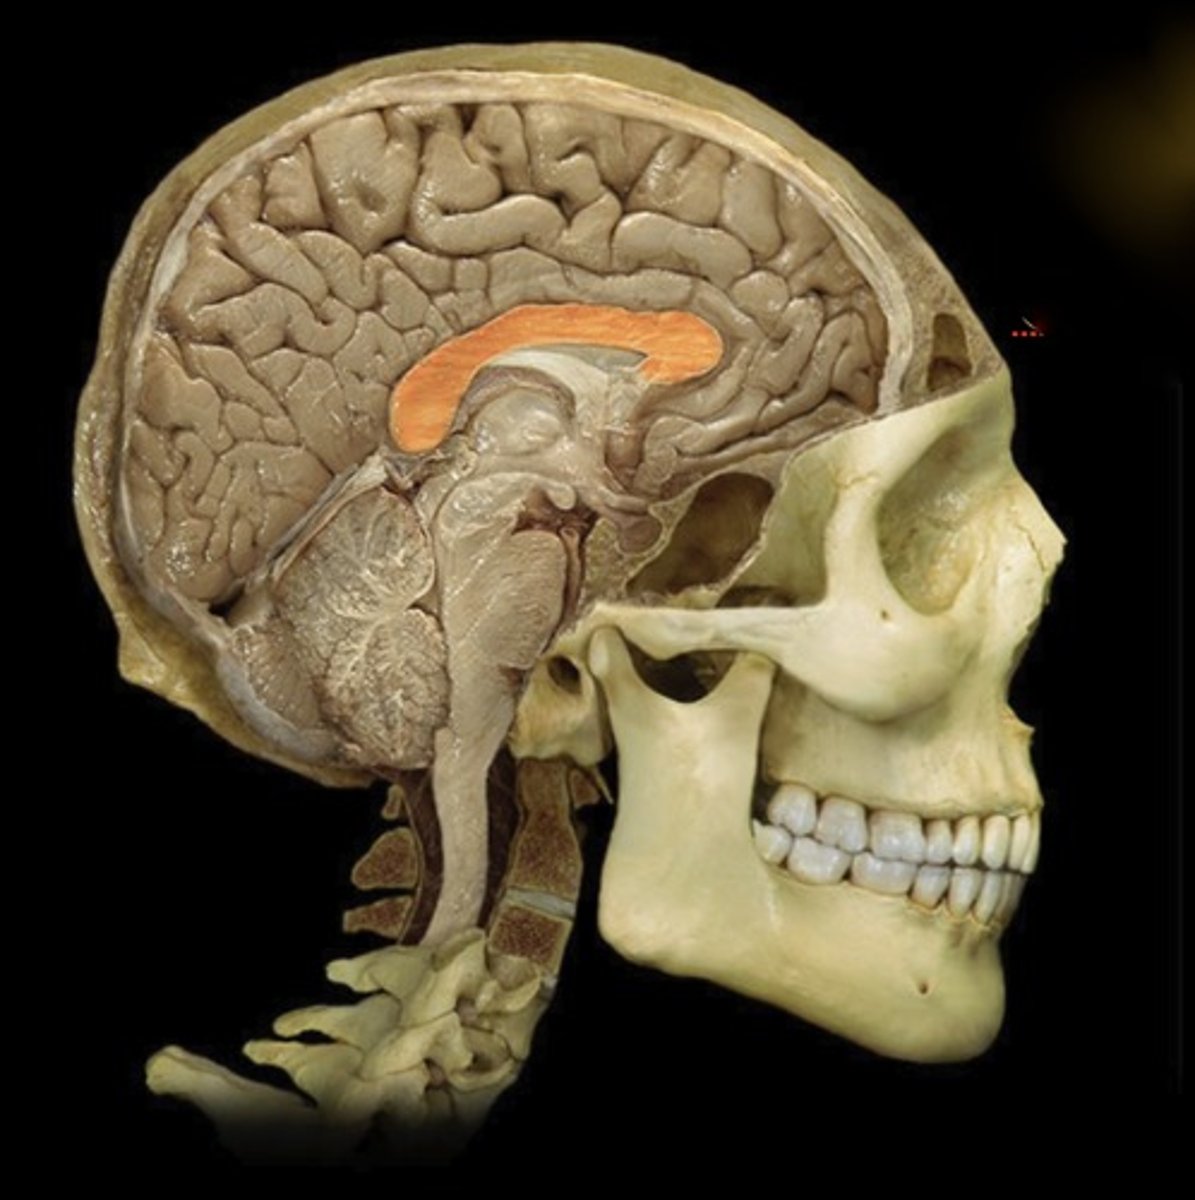

Corpus Callosum

Name this structure

Parieto-occipital sulcus

Name this structure

Thalamus

Name this structure

Hypothalamus

Name this structure

Pineal gland

Name this structure

Mamillary Body

Name this structure

Pituitary gland

Name this structure

brainstem

Name this structure

Midbrain

Name this structure

Pons

Name this structure

Medulla Oblongata

Name this structure

Cervical Spinal Cord

Name this structure

Third Ventricle

Name this structure

Fourth Ventricle

Name this structure

Fornix

Name this structure